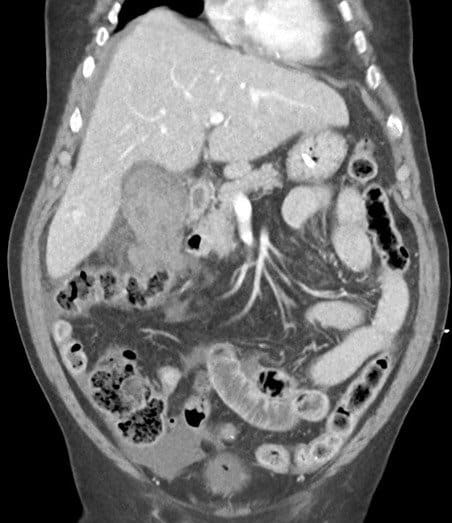

Vỡ túi mật

» Thông tin: Nam giới – 80 tuổi.

» Lâm sàng: Chấn thương.